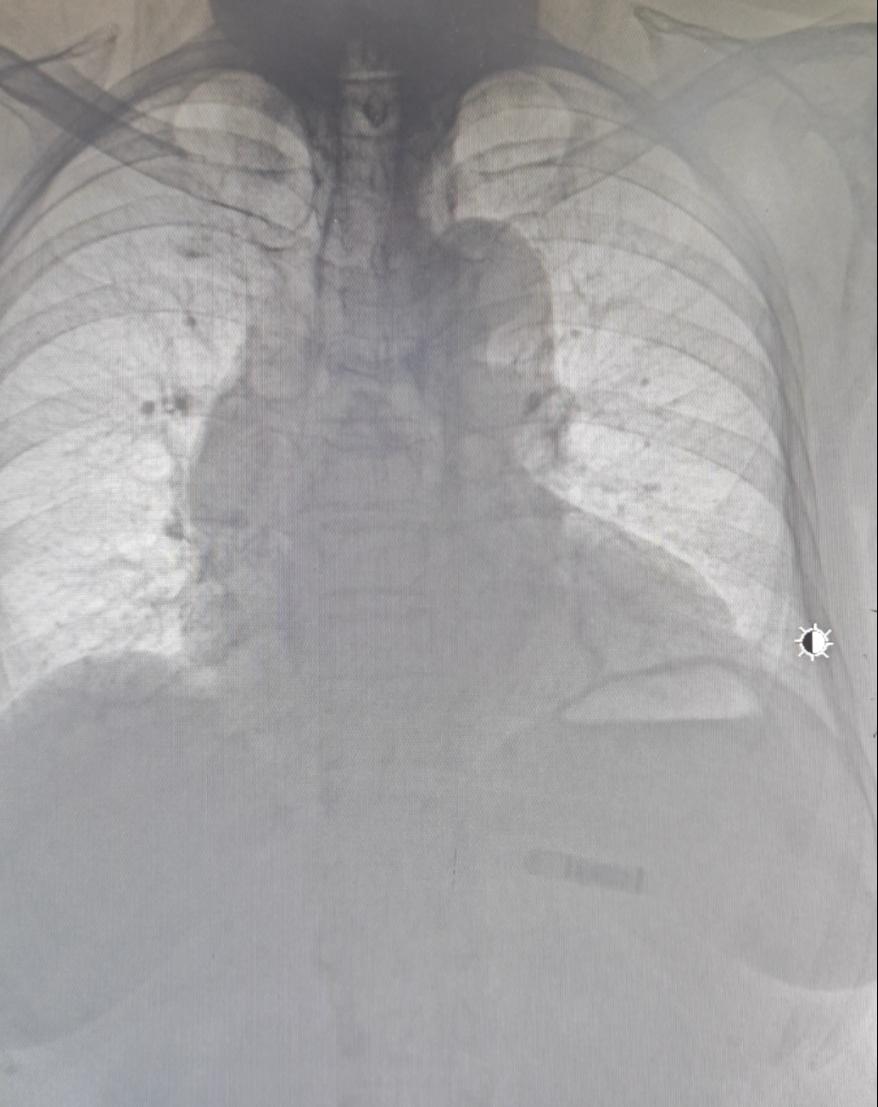

术后胸部正位片